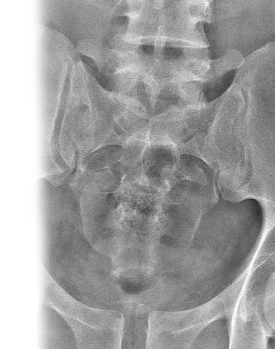

Рентгенография крестцово-подвздошного сочленения – важный метод прицельного исследования, который позволяет оценить состояние крестцово-подвздошных сочленений.

Диагностическая услуга выполняется в трех проекциях.

Рентген позволяет исключить патологию крестцово-подвздошных сочленений ревматологического, костно-травматологического, дегенеративно-дистрофического генеза.